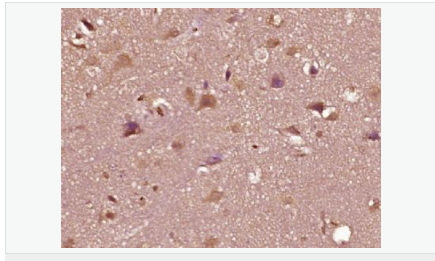

| 產(chǎn)品介紹 | The androgen receptor gene is more than 90 kb long and codes for a protein that has 3 major functional domains: the N-terminal domain, DNA-binding domain, and androgen-binding domain. The protein functions as a steroid-hormone activated transcription factor. Upon binding the hormone ligand, the receptor dissociates from accessory proteins, translocates into the nucleus, dimerizes, and then stimulates transcription of androgen responsive genes. This gene contains 2 polymorphic trinucleotide repeat segments that encode polyglutamine and polyglycine tracts in the N-terminal transactivation domain of its protein. Expansion of the polyglutamine tract causes spinal bulbar muscular atrophy (Kennedy disease). Mutations in this gene are also associated with complete androgen insensitivity (CAIS). Two alternatively spliced variants encoding distinct isoforms have been described. [provided by RefSeq, Jul 2008] Function: Steroid hormone receptors are ligand-activated transcription factors that regulate eukaryotic gene expression and affect cellular proliferation and differentiation in target tissues. Transcription factor activity is modulated by bound coactivator and corepressor proteins. Transcription activation is down-regulated by NR0B2. Activated, but not phosphorylated, by HIPK3 and ZIPK/DAPK3. [ENZYME REGULATION] AIM-100 (4-amino-5,6-biaryl-furo[2,3-d]pyrimidine) suppresses TNK2-mediated phosphorylation at Tyr-267. Inhibits the binding of the Tyr-267 phosphorylated form to androgen-responsive enhancers (AREs) and its transcriptional activity. Subunit: Binds DNA as a homodimer. Part of a ternary complex containing AR, EFCAB6/DJBP and PARK7. Interacts with HIPK3 and NR0B2 in the presence of androgen. The ligand binding domain interacts with KAT7/HBO1 in the presence of dihydrotestosterone. Interacts with EFCAB6/DJBP, PELP1, PQBP1, RANBP9, RBAK, SPDEF, SRA1, TGFB1I1, ZNF318 and RREB1. Interacts with ZMIZ1/ZIMP10 and ZMIZ2/ZMIP7 which both enhance its transactivation activity. Interacts with SLC30A9 and RAD54L2/ARIP4. Interacts via the ligand-binding domain with LXXLL and FXXLF motifs from NCOA1, NCOA2, NCOA3, NCOA4 and MAGEA11. The AR N-terminal poly-Gln region binds Ran resulting in enhancement of AR-mediated transactivation. Ran-binding decreases as the poly-Gln length increases. Interacts with HIP1 (via coiled coil domain). Interacts (via ligand-binding domain) with TRIM68. Interacts with TNK2. Interacts with USP26. Interacts with RNF6. Interacts (regulated by RNF6 probably through polyubiquitination) with RNF14; regulates AR transcriptional activity. Interacts with PRMT2 and TRIM24. Interacts with GNB2L1/RACK1. Interacts with RANBP10; this interaction enhances dihydrotestosterone-induced AR transcriptional activity. Interacts with PRPF6 in a hormone-independent way; this interaction enhances dihydrotestosterone-induced AR transcriptional activity. Interacts with STK4/MST1. Interacts with ZIPK/DAPK3. Interacts with LPXN. Interacts with MAK. Part of a complex containing AR, MAK and NCOA3. Subcellular Location: Nucleus. Cytoplasm. Note=Predominantly cytoplasmic in unligated form but translocates to the nucleus upon ligand-binding. Can also translocate to the nucleus in unligated form in the presence of GNB2L1. Tissue Specificity: Isoform 2 is mainly expressed in heart and skeletal muscle. Post-translational modifications: Sumoylated on Lys-386 (major) and Lys-520. Ubiquitinated. Deubiquitinated by USP26. 'Lys-6' and 'Lys-27'-linked polyubiquitination by RNF6 modulates AR transcriptional activity and specificity. Phosphorylated in prostate cancer cells in response to several growth factors including EGF. Phosphorylation is induced by c-Src kinase (CSK). Tyr-534 is one of the major phosphorylation sites and an increase in phosphorylation and Src kinase activity is associated with prostate cancer progression. Phosphorylation by TNK2 enhances the DNA-binding and transcriptional activity and may be responsible for androgen-independent progression of prostate cancer. Phosphorylation at Ser-81 by CDK9 regulates AR promoter selectivity and cell growth. Phosphorylation by PAK6 leads to AR-mediated transcription inhibition. Palmitoylated by ZDHHC7 and ZDHHC21. Palmitoylation is required for plasma membrane targeting and for rapid intracellular signaling via ERK and AKT kinases and cAMP generation. DISEASE: Defects in AR are the cause of androgen insensitivity syndrome (AIS) [MIM:300068]; previously known as testicular feminization syndrome (TFM). AIS is an X-linked recessive form of pseudohermaphroditism due end-organ resistance to androgen. Affected males have female external genitalia, female breast development, blind vagina, absent uterus and female adnexa, and abdominal or inguinal testes, despite a normal 46,XY karyotype. Defects in AR are the cause of spinal and bulbar muscular atrophy X-linked type 1 (SMAX1) [MIM:313200]; also known as Kennedy disease. SMAX1 is an X-linked recessive form of spinal muscular atrophy. Spinal muscular atrophy refers to a group of neuromuscular disorders characterized by degeneration of the anterior horn cells of the spinal cord, leading to symmetrical muscle weakness and atrophy. SMAX1 occurs only in men. Age at onset is usually in the third to fifth decade of life, but earlier involvement has been reported. It is characterized by slowly progressive limb and bulbar muscle weakness with fasciculations, muscle atrophy, and gynecomastia. The disorder is clinically similar to classic forms of autosomal spinal muscular atrophy. Note=Caused by trinucleotide CAG repeat expansion. In SMAX1 patients the number of Gln ranges from 38 to 62. Longer expansions result in earlier onset and more severe clinical manifestations of the disease. Note=Defects in AR may play a role in metastatic prostate cancer. The mutated receptor stimulates prostate growth and metastases development despite of androgen ablation. This treatment can reduce primary and metastatic lesions probably by inducing apoptosis of tumor cells when they express the wild-type receptor. Defects in AR are the cause of androgen insensitivity syndrome partial (PAIS) [MIM:312300]; also known as Reifenstein syndrome. PAIS is characterized by hypospadias, hypogonadism, gynecomastia, genital ambiguity, normal XY karyotype, and a pedigree pattern consistent with X-linked recessive inheritance. Some patients present azoospermia or severe oligospermia without other clinical manifestations. Similarity: Belongs to the nuclear hormone receptor family. NR3 subfamily. Contains 1 nuclear receptor DNA-binding domain. SWISS: P10275 Gene ID: 367 Database links: Entrez Gene: 367 Human Entrez Gene: 11835 Mouse Omim: 313700 Human SwissProt: P10275 Human SwissProt: P19091 Mouse Unigene: 496240 Human Unigene: 39005 Mouse Unigene: 394224 Mouse Unigene: 439657 Mouse Unigene: 9813 Rat Important Note: This product as supplied is intended for research use only, not for use in human, therapeutic or diagnostic applications. AR是一個(gè)由917個(gè)氨基酸組成的蛋白質(zhì),位于雄激素靶組織細(xì)胞中或細(xì)胞表面上的特異分子部位或結(jié)構(gòu)。 AR在前列腺癌中起著重要的作用,研究表明AR的表達(dá)與組織分型形成一定的相關(guān)性 ,AR在高分化的腫瘤中表達(dá)較多,而在低分化的腫瘤中表達(dá)較少。用于前列腺癌的檢測(cè),指導(dǎo)臨床治療,目前可用于乳腺癌、食道癌等各項(xiàng)腫瘤的研究。 |